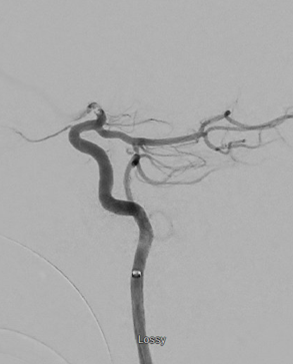

It's always important to understand #anatomy even during an #ICA terminus occlusion - how would you classify this pcomm artery? Comment below! #stroke CV Section ESMINT Society

It's always important to understand #anatomy even during an #ICA terminus occlusion - how would you classify this pcomm artery? Comment below!

#stroke <a href="/cvsection/">CV Section</a> <a href="/esmintsociety/">ESMINT Society</a>